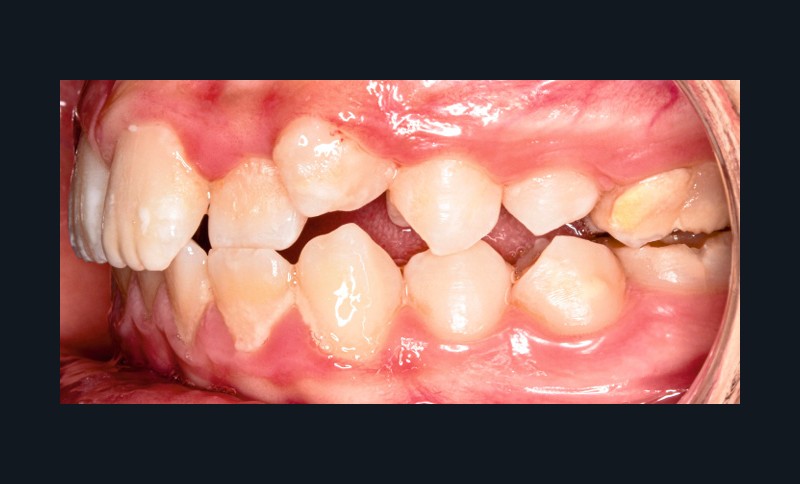

Sur le plan alvéolo-dentaire (fig. 1b) :

- Classe II subdivision gauche avec déviation du point inter-incisif mandibulaire à gauche ;

- occlusion inversée entre 22 et 32 ;

- dysharmonie dento-arcade (DDA) sévère ;

- 13 en position haute retenue.

Sur le plan squelettique : Classe II, schéma hypodivergent (fig. 1c). Sur le plan fonctionnel : aucune dysfonction ni parafonction.